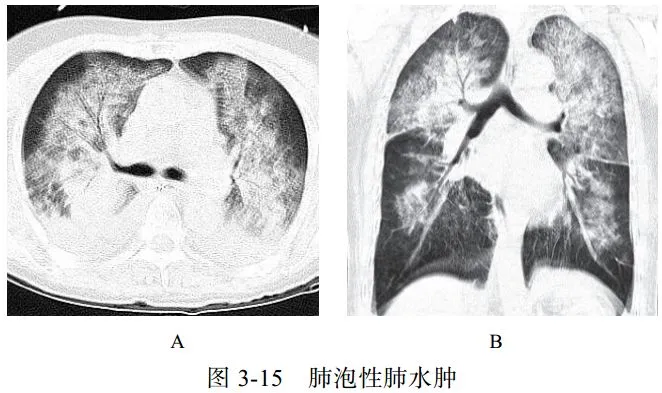

(一)肺泡性肺水肿

肺水肿病理上分为间质性肺水肿和肺泡性肺水肿,严重者常两种情况并存,心源性肺水肿居多。肺泡性肺水肿液体在肺泡内聚集呈片状,肺体积增大,有液体外渗,合并充血时渗液呈红色或棕色,急性期表现为气急、端坐呼吸、咳泡沫白痰或粉红色痰,可闻及湿啰音,可同时出现全身静脉压升高及肝脾大的表现

影像学表现:

(1)典型蝶翼征(图 3-15A),两肺散布大小不等、密度不均、轮廓不清的片状模糊影(图 3-15B),局限性表现为一侧、一叶或局部的密度增高影

(2)心源性肺水肿可见双侧上肺静脉扩张,心影增大,可合并胸腔积液、心包积液